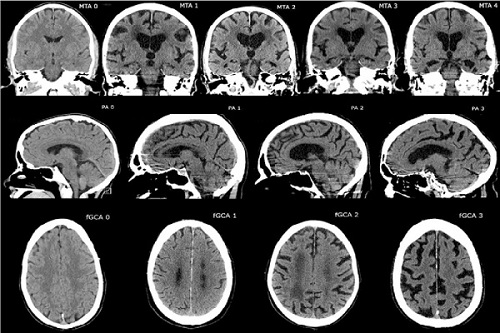

Uno de los casos más comunes de atrofia cerebral es la que se caracteriza por acercamiento entre las superficies corticales y epindimarias, ensanchamiento de los surcos cerebrales, y adelgazamiento de las circunvoluciones de los lóbulos frontales.

De hecho, el envejecimiento implica una reducción progresiva de las conexiones y de las estructuras cerebrales. Para poder distinguir una atrofia patológica de una atrofia benigna asociada a la edad resulta importante llevar a cabo una adecuada exploración neuropsicológica que especifique las características del deterioro cognitivo.

Los síntomas más típicos del Alzheimer son la pérdida de la memoria, ya que la atrofia cerebral la produce inicialmente en el hipocampo (estructura que se encarga de desarrollar los procesos mnésicos).

No obstante, con la progresión de la enfermedad la atrofia se prolonga hacía las otras regiones cerebrales, produciendo muchos más déficits cognitivos.